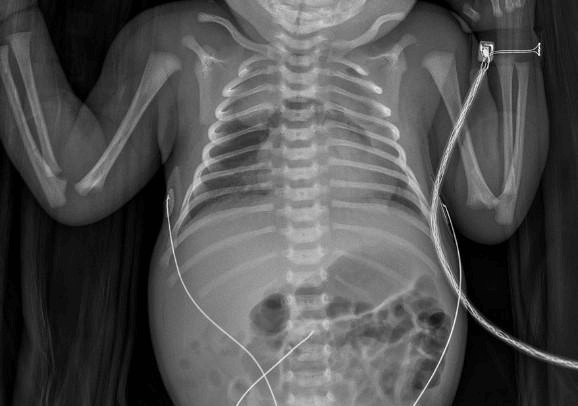

A male term newborn was born from a monitored and uneventful 38 weeks gestation via an elective caesarean section with Apgar scores of 8/8/8 at first, fifth and tenth minutes respectively and with a birth weight of 2980 g. Two minutes after birth he began to have irregular respiratory movements and started intermittent positive pressure ventilation followed by alveolar recruitment. Since he maintained signs of respiratory distress he was admitted to a neonatal intensive care unit (NICU) and was put on continuous positive airway pressure (CPAP) of 4,5 cm H2O and fraction of inspired oxygen of 0,30. Laboratory markers for infection were negative and arterial blood gas excluded respiratory or metabolic acidosis. Two hours after admission in the NICU, the newborn showed signs of clinical improvement and suspended CPAP, beginning spontaneous breathing with no need of supplemental oxygen and with arterial oxygen saturation above 94%. An anterior-posterior chest-radiography (CXR) at six hours of life revealed a hyperlucency around the left cardiac border and wedge-shaped opacities of the upper third of the right hemithorax and of the two upper thirds of the left hemithorax (Figure 1). For better understanding of this image, a low-radiation axial computed tomography (CT-scan) of the chest was performed revealing a normal airway and pulmonary parenchyma and a centered mediastinum showing evidence of a small amount of air. Pulmonary congenital malformations or other masses were excluded. Since the newborn remained haemodynamically stable, the clinicians opted for a conservative approach. There was a favorable clinical evolution and he was discharged at four days of age, asymptomatic and with radiological improvement. Follow-up after four weeks revealed a full radiographic resolution.

Figure 1. Hyperlucency around the left cardiac border and wedge-shaped opacities of the upper third of the right hemithorax and of the two upper thirds of the left hemithorax, raising suspicion of a pneumomediastinum.

Pneumomediastinum’s diagnosis is based on clinical presentation and imaging findings.4,11 In most cases, CRX is enough to confirm the diagnosis, especially when the pathognomonic spinnaker-sail sign is present.2,6,12,13 Both thymus lobes are lifted and displaced laterally due to the air in the mediastinum. This creates a wedge-shaped opacity that extends into the superior mediastinum and that is sharply outlined inferiorly by translucent mediastinal air.6,10,13